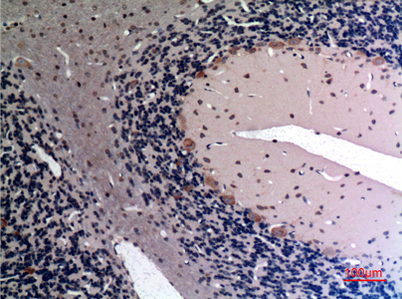

Product name: FGF-12 rabbit pAb

Dilutions: Western Blot: 1/500 - 1/2000. IHC-p: 1:100-300 ELISA: 1/20000. Not yet tested in other applications.

Immunogen: The antiserum was produced against synthesized peptide derived from the Internal region of human FGF12. AA range:31-80